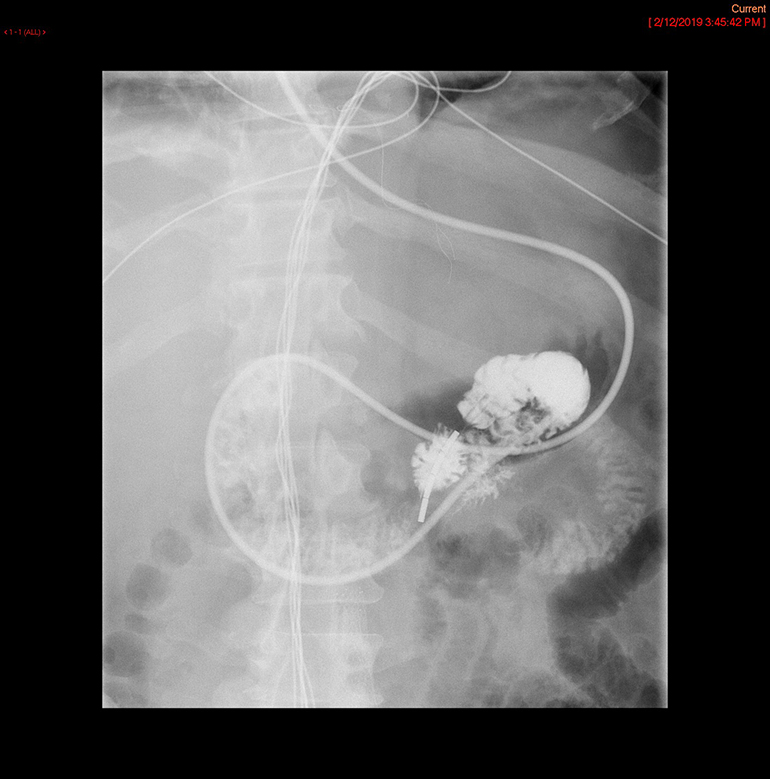

- The technologist will obtain a scout radiograph to include the upper abdomen. Evaluate for the location of the surgical chain sutures

(key image 1).

- There are usually two "sets" of surgical chain sutures.

- The first is located in the epigastric area at the level of the gastrojejunal anastomosis.

- The second is usually located in the left midabdomen. This is the site of the jejunojejunal anastomosis.

- Obtain a spot film of the contrast material filling the gastric pouch and proximal roux limb

(key image 2).

- The technologist will take a post procedure radiograph to evaluate the upper abdomen

(key image 4).

- If the contrast material has not progressed beyond the jejunojejunal anastomosis on the first radiograph, have the technologist obtain a delayed radiograph (more than one may be needed). Once the contrast has progressed past the jejunojejunal anastomosis, the procedure is complete

(key image 5)

(key image 6)

(key image 7).